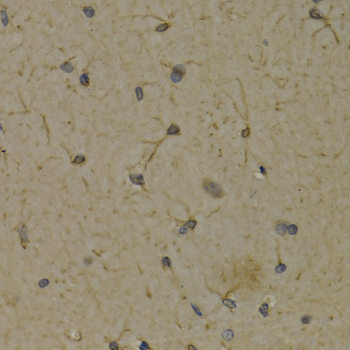

• A2158: image 2

Immunohistochemistry of paraffin-embedded rat brain using ALOX5 antibody at dilution of 1:200 (400x lens).